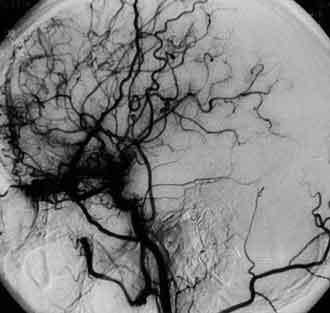

是脑血管畸形吗?行脑血管数字造影果然发现:双侧颈内动脉均匀性狭窄、C1段末端与M段A1交界处大量新生烟雾状血管。

原来,导致脑梗死的罪魁祸首是----烟雾病!

(烟雾病,又称Moyamoya病,是一种脑血管疾病,特点为双侧颈内动脉终末部分狭窄或闭塞,伴随基底节区出现网状样侧副血管,它是引起脑卒中的一种少见病因。)

烟雾病,颅底出现大量异常新生小血管网,显影后酷似吸烟时吐出的烟雾,故得名。